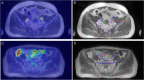

Purpose: A comparative retrospective study to assess the impact of PSMA Ligand PET/MRI ([68 Ga]-Ga-PSMA-11 and [18F]-F-PSMA-1007 PET/MRI) as a new method of target delineation compared to conventional imaging on whole-pelvis radiotherapy for high-risk prostate cancer (PCa).

Patients and methods: Forty-nine patients with primary high-risk PCa completed the whole-pelvis radiotherapy plan based on PSMA PET/MRI and MRI. The primary endpoint compared the size and overlap of clinical target volume (CTV) and nodal gross tumour volume (GTVn) based on PSMA PET/MRI and MRI. The diagnostic performance of two methods for pelvic lymph node metastasis (PLNM) was evaluated.

Results: In the radiotherapy planning for high-risk PCa patients, there was a significant correlation between MRI-CTV and PET/MRI-CTV (P = 0.005), as well as between MRI-GTVn and PET/MRI-GTVn (P < 0.001). There are non-significant differences in the CTV and GTVn based on MRI and PET/MRI images (P = 0.660, P = 0.650, respectively). The conformity index (CI), lesion coverage factor (LCF) and Dice similarity coefficient (DSC) of CTVs were 0.999, 0.953 and 0.954. The CI, LCF and DSC of GTVns were 0.927, 0.284, and 0.32. Based on pathological lymph node analysis of 463 lymph nodes from 37 patients, the sensitivity, specificity of PET/MRI in the diagnosis of PLNM were 77.78% and 99.76%, respectively, which were higher than those of MRI (P = 0.011). Eight high-risk PCa patients who finished PSMA PET/MRI changed their N or M stage.

Conclusion: The CTV delineated based on PET/MRI and MRI differ little. The GTVn delineated based on PET/MRI encompasses metastatic pelvic lymph nodes more accurately than MRI and avoids covering pelvic lymph nodes without metastasis. We emphasize the utility of PET/MRI fusion images in GTVn delineation in whole pelvic radiotherapy for PCa. The use of PSMA PET/MRI aids in the realization of more individual and precise radiotherapy for PCa.